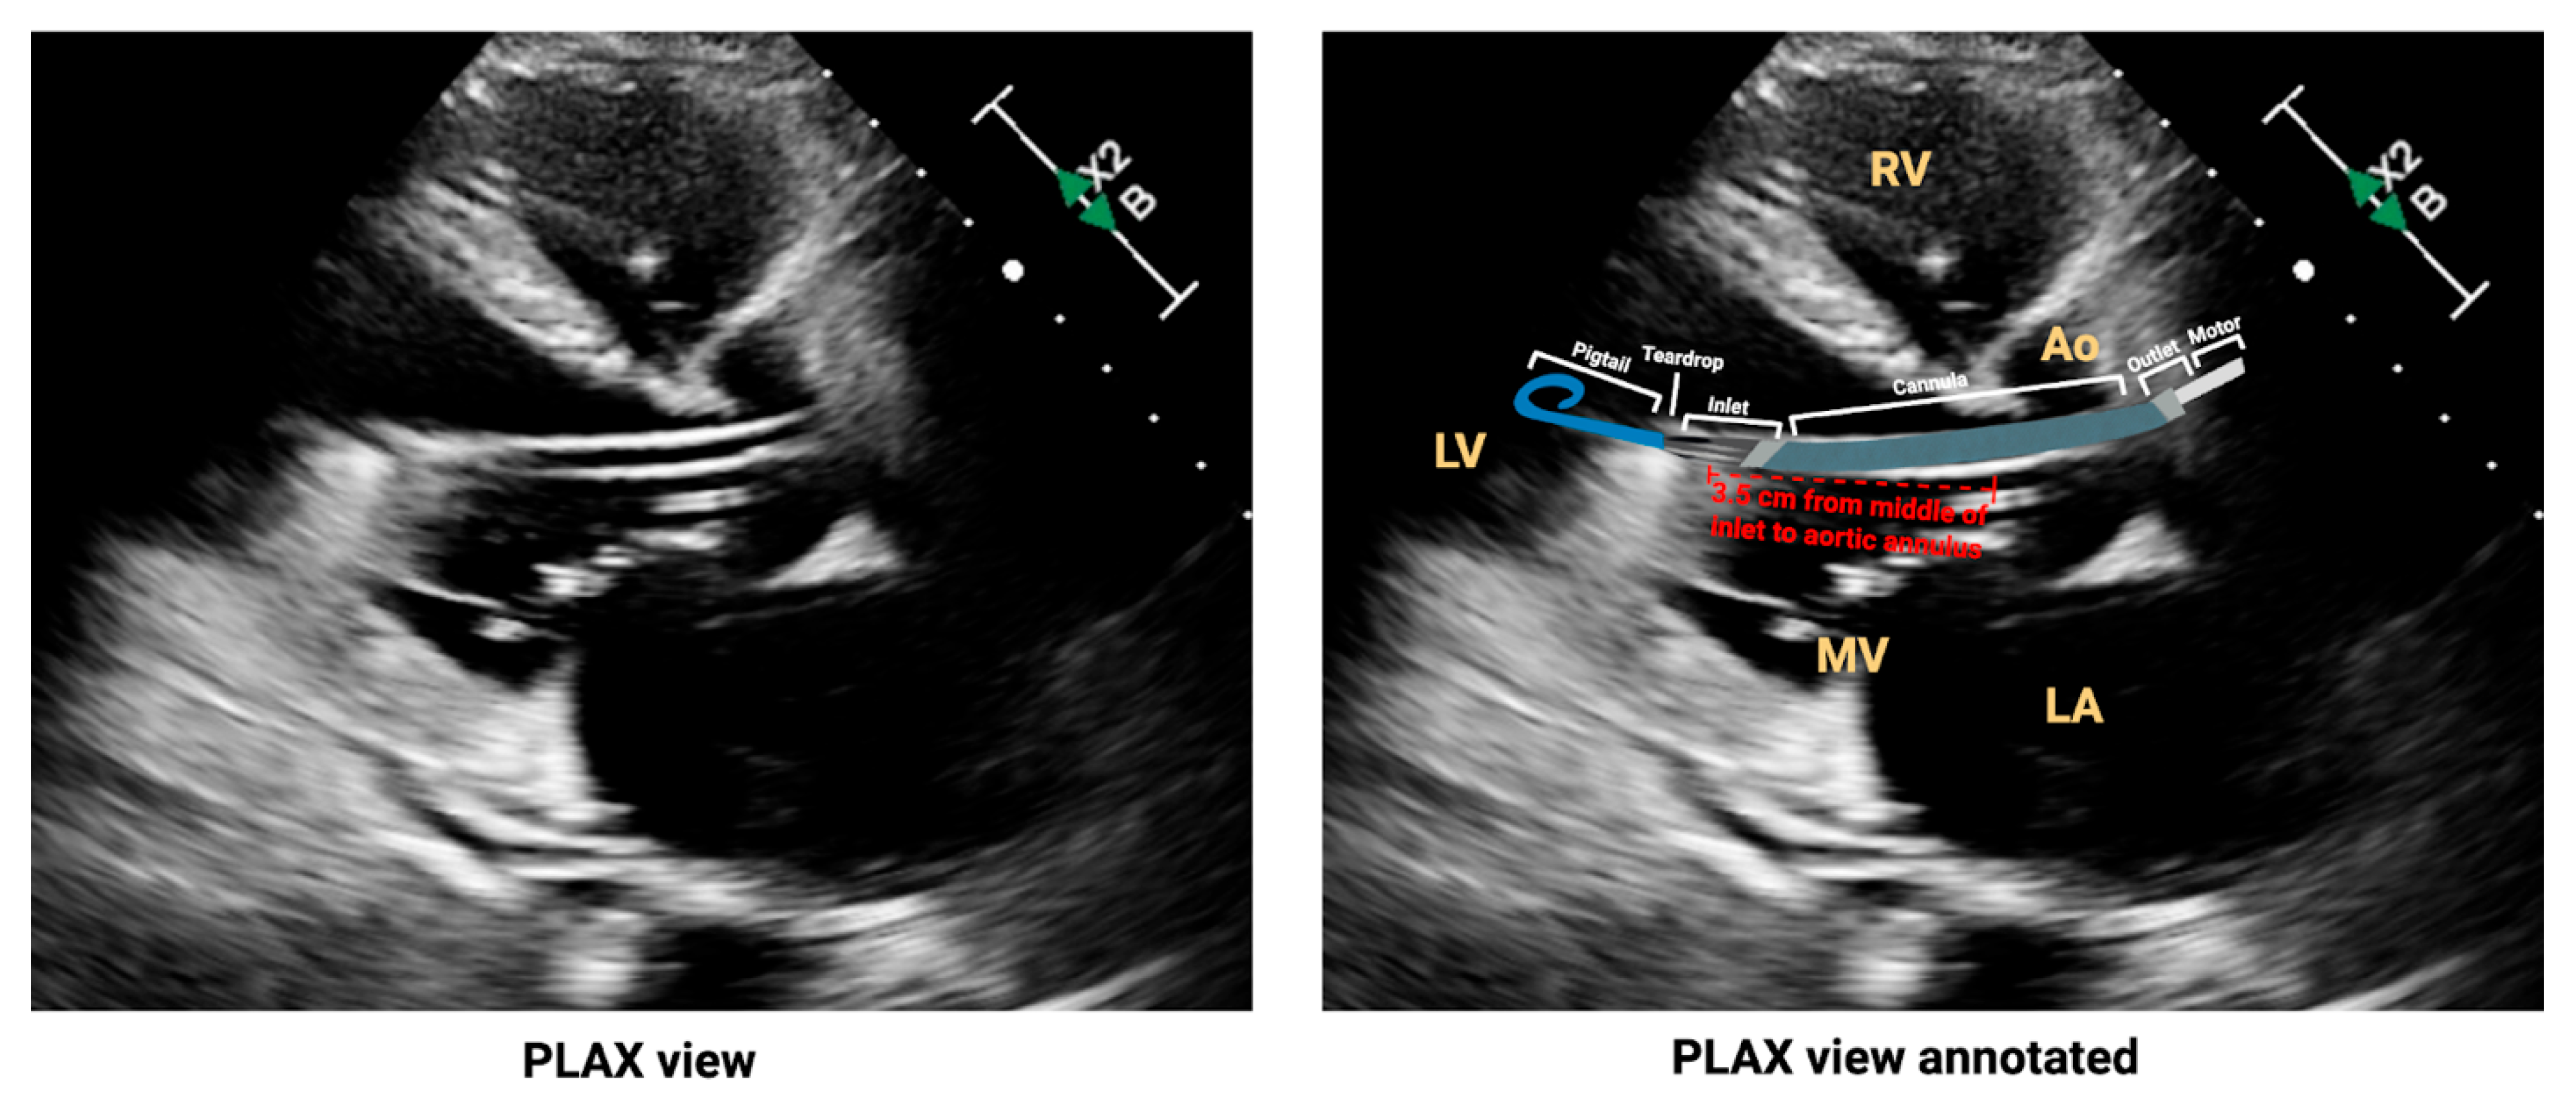

- Tran, T.; Mudigonda, P.; Mahr, C.; Kirkpatrick, J. Echocardiographic imaging of temporary percutaneous mechanical circulatory support devices. J. Echocardiogr. 2022, 20, 77–86. [Google Scholar] [CrossRef]

- Sacks, S.; Feinman, J. A 2024 Update From the American Society of Echocardiography: Multimodality Imaging for Patients With Left Ventricular Assist Devices and Temporary Mechanical Circulatory Support. J. Cardiothorac. Vasc. Anesth. 2025, 39, 1919–1923. [Google Scholar] [CrossRef]